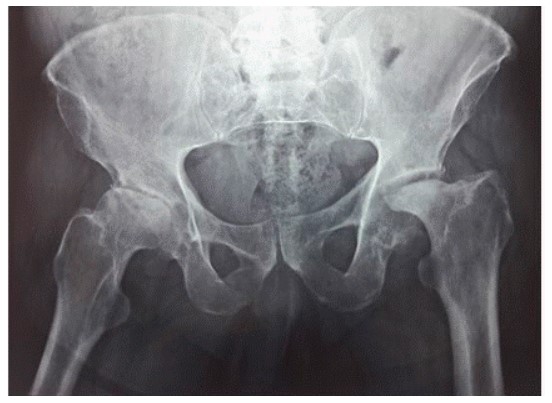

La osteonecrosis como la de Jacinto, paciente que acudió a nuestra consulta por osteonecrosis bilateral de fémur, se debió al uso crónico de corticoides por una enfermedad autoinmune.

Inicialmente el hueso y la médula ósea se degeneran manteniéndose vivo el cartílago que se alimenta de los nutrientes del líquido sinovial. Aparecen lesiones líticas con destrucción de la matriz trabecular y reemplazo en los huecos por tejido graso. La imagen radiológica no es muy llamativa, pero hay dolor y daño en los tejidos analizados al microscopio.

Posteriormente la lesión más clara se subraya con una imagen de esclerosis alrededor como si el hueso sano circundante intentara rodear la lesión, lo que además es más marcado en la gammagrafía.

En la última, hay destrucción, fractura y separación de los fragmentos óseos dañados, acompañando al cartílago sano que pierde el soporte. En suma, se hunde la superficie articular por destrucción de los pilares que constituyen la trama ósea.

La sintomatología de dolor en la ingle en reposo y a la exploración, y en los esfuerzos, giros y movimientos, es progresivamente invalidante y el diagnóstico radiológico suele confirmar las sospechas.